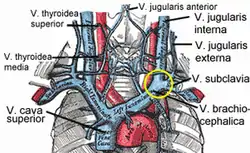

| Veins of the neck. V.jugularis interna is proposed to be stenosed or have a malformed valve in CCSVI cases. | |